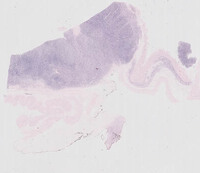

Figure 2: H&E Low Power in Plasmacytoma-Like PTLD, EBV+

The image on the left shows low power of the entire bowel wall with normal small bowel mucosa on the top with extensive infiltration of the muscularis propria and submucosa by a sheetlike infiltrate of neoplastic cells.

The image on the right shows the neoplastic cells at higher power present in sheets percolating in between the fibers of the muscularis propria.